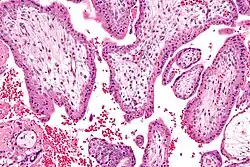

Durante a quarta semana de idade gestacional (segunda semana de idade embrionária), as células trofoblásticas que envolvem as células embrionárias penetram profundamente no revestimento uterino, formando a placenta e as membranas embrionárias. Começa-se também a formar a vesícula vitelina, as células embrionárias formam um disco embrionário com duas células de espessura, desenvolve-se a linha primitiva e aparecem as vilosidades coriónicas. Na quinta semana de idade gestacional (terceira semana de idade embrionária) tem início a gastrulação, forma-se a corda dorsal no centro do disco embrionário, começa-se a formar o que virá a ser a medula espinal, com uma saliência que corresponderá ao cérebro, e aparecem os primeiros neurómeros. Já no final da semana, começam também a formar-se os vasos do coração primitivo e a desenvolver-se vascularização no disco embrionário.[44]

A placenta é uma estrutura em forma de disco que envolve e protege o feto e o líquido amniótico. No termo da gravidez, pesa entre 500 e 1 000 gramas, mede 16 a 20 cm de diâmetro e 3 a 4 cm de espessura. Este órgão encontra-se unido às vilosidades coriónicas que revestem todo o útero, tem aparência lisa e brilhante e é constituída por diversos vasos sanguíneos que se unem no ponto onde começa o cordão umbilical. O sangue materno flui entre os vasos uterinos e o espaço interviloso, onde se acumula. Em cada vilosidade existe uma rede de vasos sanguíneos que fazem parte do sistema circulatório fetal e cuja circulação é impulsionada pelo coração do feto. Esta divisão entre a circulação materna e fetal denomina-se barreira placentária. À medida que a gravidez avança, a barreira torna-se mais fina. Esta barreira impede a passagem de células sanguíneas e de bactérias, embora permita a passagem de nutrientes, sal, vírus, hormonas e diversas substâncias, entre as quais drogas nocivas ao feto.[1]

A biópsia das vilosidades coriónicas é um exame de diagnóstico que consiste na recolha de uma amostra das vilosidades coriónicas do útero, as membranas embriónicas exteriores. Embora semelhante à amniocentese, este exame pode ser realizado bastante mais cedo, geralmente entre as oito e doze semanas de gestação, o que em caso de resultados desfavoráveis permite optar pela interrupção da gravidez numa fase precoce. Por ser realizado mais cedo, apresenta um risco de aborto espontâneo significativamente superior ao da amniocentese (1-2%).[1][72]